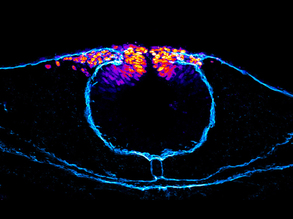

Eye Breakdown